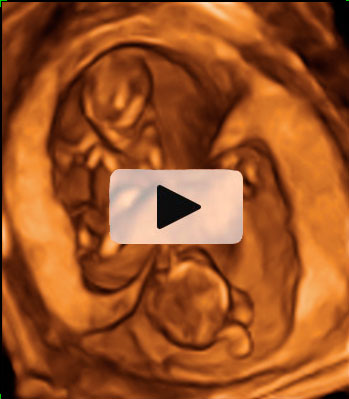

Ecografía semana 11: Bebé moviéndose en el útero

El bienestar fetal de este bebé de 11 semanas de gestación parece evidente a juzgar por su movimiento de brazos y piernas. Esta ecografía 4D ofrece el "baile" de este pequeñín, que está finalizando su primer trimestre de embarazo.

Ecografía en 4D de feto de 11 semanas moviéndose

Feto de 11 semanas de gestación con brazos y piernas en movimiento continuo dentro del útero materno. No se aprecian las extremidades con nitidez debido al "corte" de imagen que selecciona el ecografista.